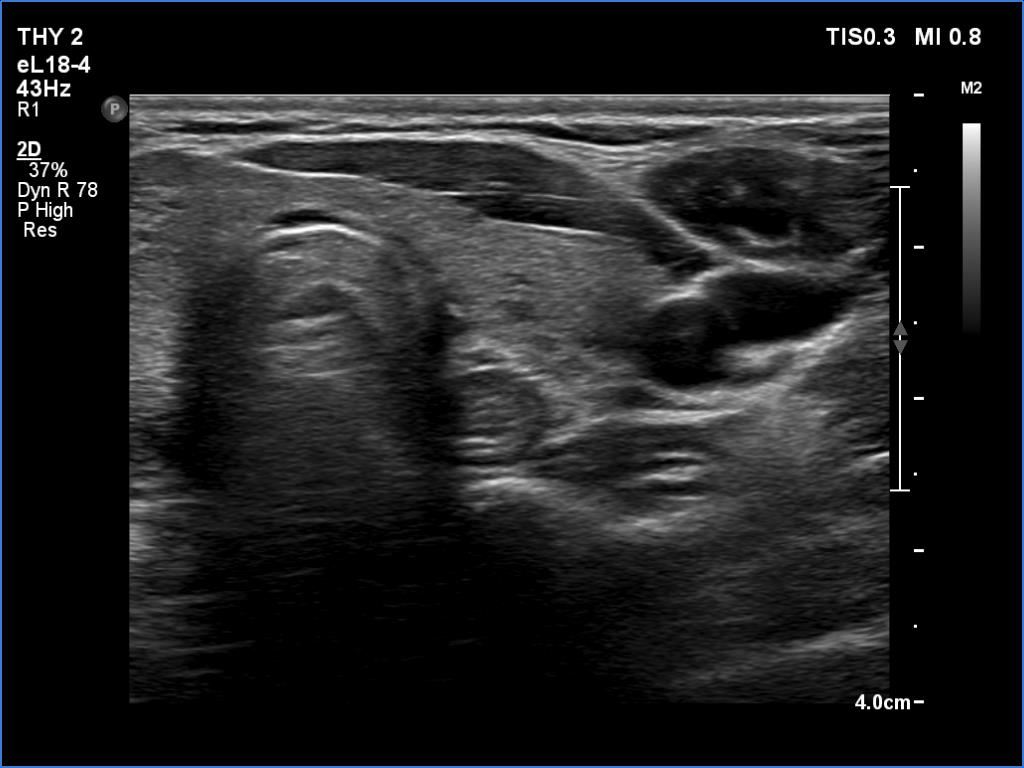

Right lobe, longitudinal scan

Left lobe, transverse scan. This lobe alaso presents hypoechoic areas.